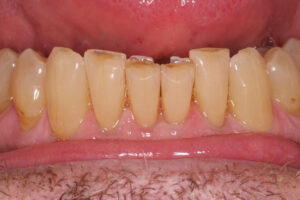

- Len Before – Chipped Teeth

- Len After – Chipped Teeth